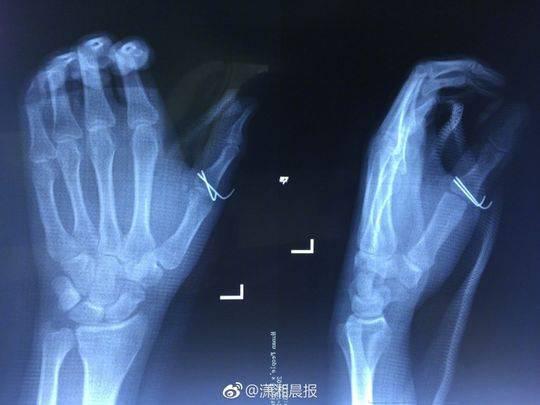

劇烈的疼痛讓小袁發出慘叫,家人聞訊趕來一看,只見他的傷口血流不止,受傷的左手也動彈不得,隨即將他送往湖南省人民醫院急診一科就診,醫生為其傷口進行了緊急處理。X 光檢查發現,小袁的左手拇指近節指骨骨折,需進行手術固定,于是將他收入創傷骨病科病房。

當晚10點,該院創傷骨病科何畔副主任醫師等為小袁施行 “ 左手清創探查、左拇指近節指骨骨折切開復位 + 克氏針內固定術 ”,手術歷時 2小時順利完成。術后,小袁的左手需采用石膏固定4~6周。